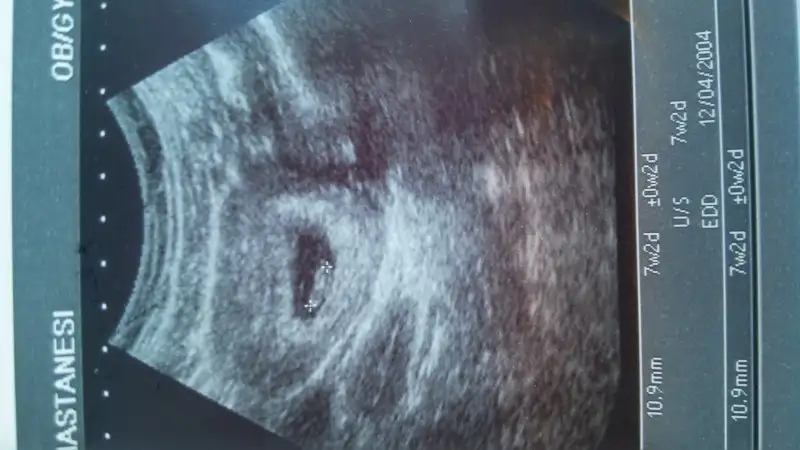

Erkek gibi cnmKızlar bana bidaha bakin persembe yine gidecem ama usg almadim en sin gittigimde

söylemişti o zaman doktorCnm yolk sac olduğunu nerden bildin,doktor + işaretiyle bebegin olduGu yeri işaretlemis.

evet ultrason karındancanım ultrason karındansa erkek, vajinal ise kız bebişin olma ihtimali yüksek. Allah gönlüne göre versin tatlım :)

mrb canım ben ilk önce ulrason görüntülerini büyük sandım. o yüzden plasenta yönü yorumu yapmadım ama ikinci foto 7+3 günlükmüş. orda plasenta sağ altta görünüyor şayet ultrason karındansa kız, vajinal ise erkek olma ihtimali yüksek canım. allah gönlüne göre versin canım.Kızlar bana bidaha bakin persembe yine gidecem ama usg almadim en sin gittigimde Eki Görüntüle 1711090 Eki Görüntüle 1711088 Eki Görüntüle 1711088 Eki Görüntüle 1711089 Eki Görüntüle 1711090 Eki Görüntüle 1711089

Erkek canim soldadir bebisin :)Kizlar benimkini yorumlar misiniz lutfeeeeeen :) karindan görüntü

7+3 de karından canim ilk olan usg 5 haftalık olan vajinal insallah dedigin gibidir canim yaamrb canım ben ilk önce ulrason görüntülerini büyük sandım. o yüzden plasenta yönü yorumu yapmadım ama ikinci foto 7+3 günlükmüş. orda plasenta sağ altta görünüyor şayet ultrason karındansa kız, vajinal ise erkek olma ihtimali yüksek canım. allah gönlüne göre versin canım.

Arkadaşlar hep erkek demiş ama ben plasentayı sağ altta gibi gördüm canım. Karından ultrason da sağ altta ise kız deniyor. Senin gönlün hangi cinsiyetten yana ise o olur inşallah :)7+3 de karından canim ilk olan usg 5 haftalık olan vajinal insallah dedigin gibidir canim yaa